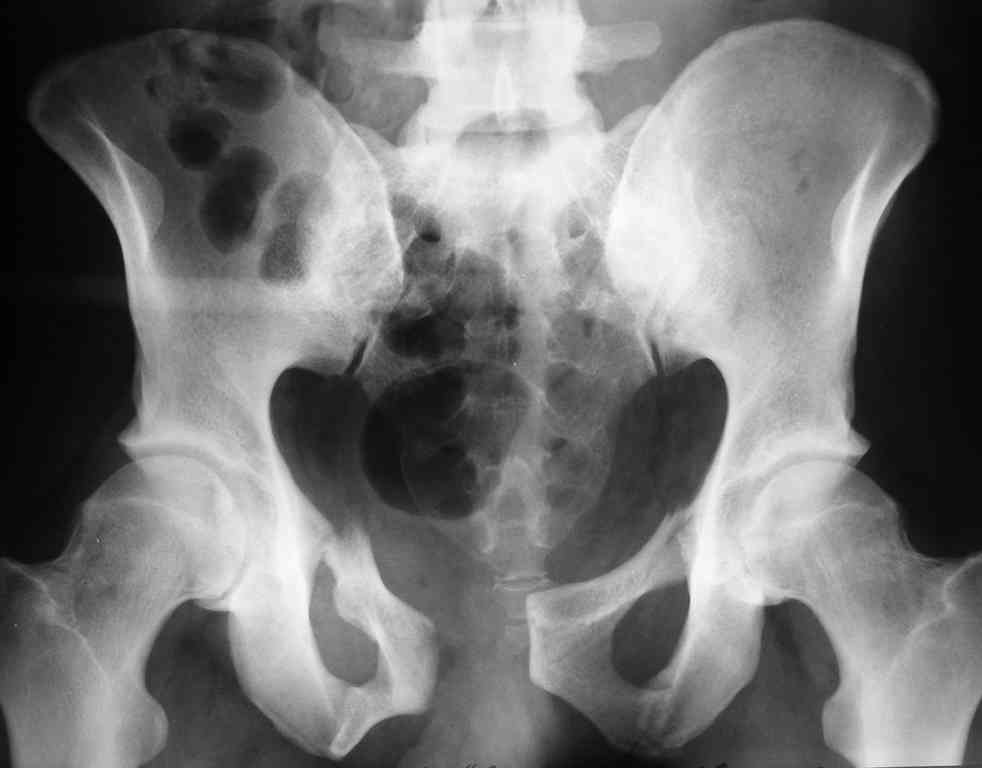

Уважаемые коллеги! опять вопрос по повреждению таза. Больной получил производственную травму 10 дней назад - удар балкой около 3 тонн в область верхней трети правого бедра и лона.

Был диагностирован перелом "типа бабочки" и повреждение уретры. Сделана цистостома. У насв отделении 3 дня. Имеется огромная флюктуирующая гематома с "галифе"-образной деформацией обеих бедер. Пнкционно эвакуировали в несколько приемов из подфасциальных полостей на бедрах около 3 литров геморрагического отделяемого с последующей эластической компрессией. При пункциях выявлено сообщение полостей на бедрах - видимо через поравннуюдиафрагму дна и полость таза - при удалении крови справа уменьшался объем левого бедра. Какой то активности проявялять покабоимся - аппаратная фиксация через отслоенные ткани представляется чреватой нагноением, открытая фиксация в условиях такой гематомы тоже не радует. Хотелось бы услышать ваше мнение

Типичная картина Morel-Lavallee повреждения.